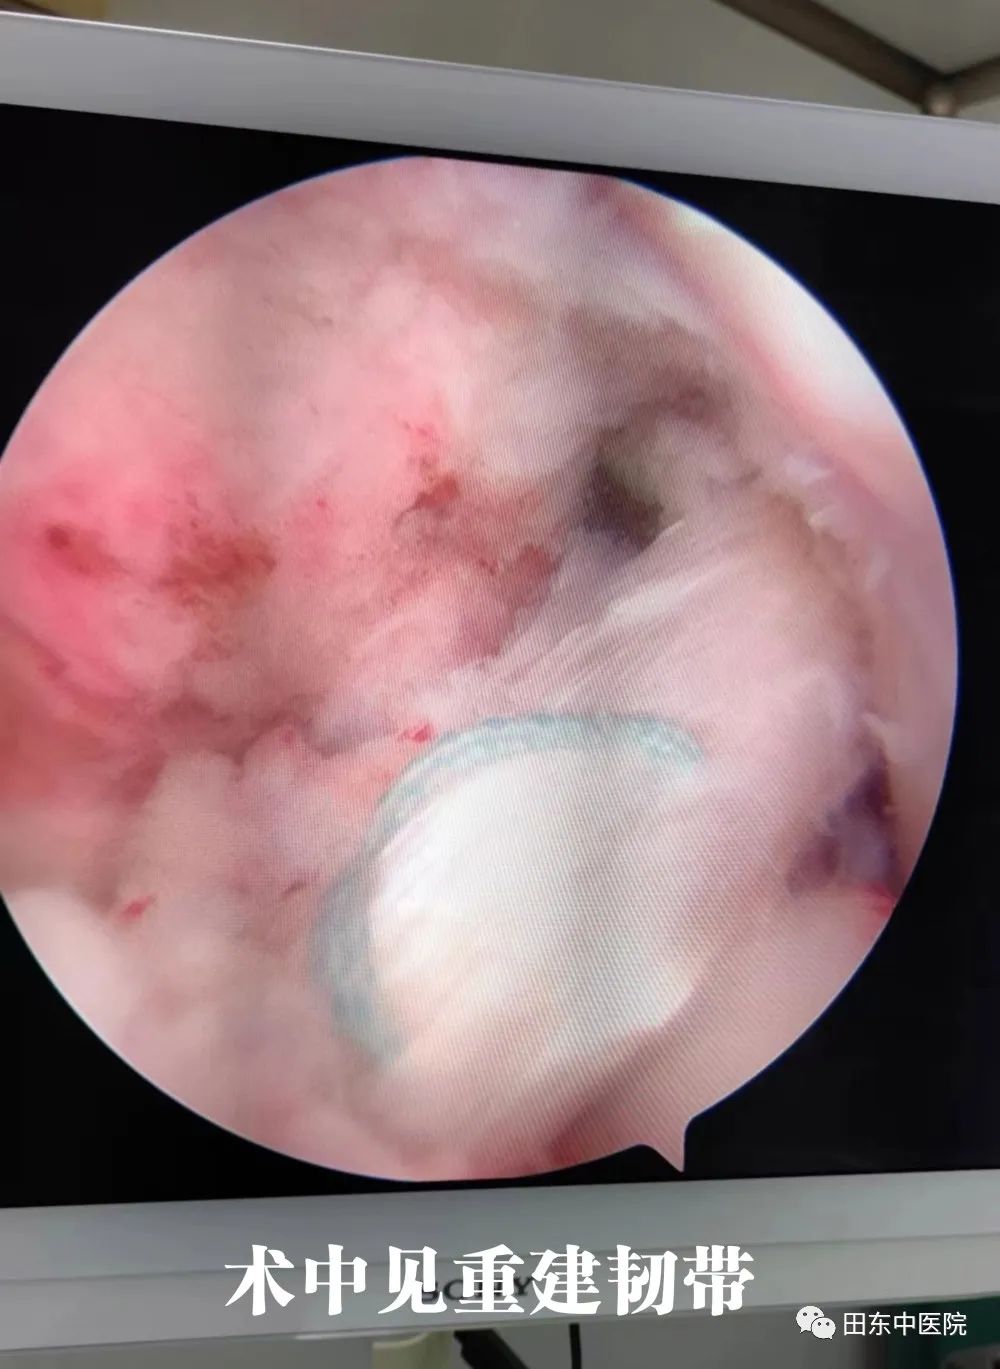

2022年8月2日,我院骨伤科二区在深圳平乐骨伤科医院李长树主治医师和骨二区农达杰主任带领下,顺利完成了我院首例膝关节镜下前交叉韧带自体腱单骨道重建、外侧半月板修切成形,关节清理,射频治疗术。

手术在李长树主治医师及农达杰主任主刀下顺利完成。手术过程顺利,在我院骨科团队细心指导与精心照料下,陈阿姨状态恢复良好。术后患者关节稳定,功能恢复正常。